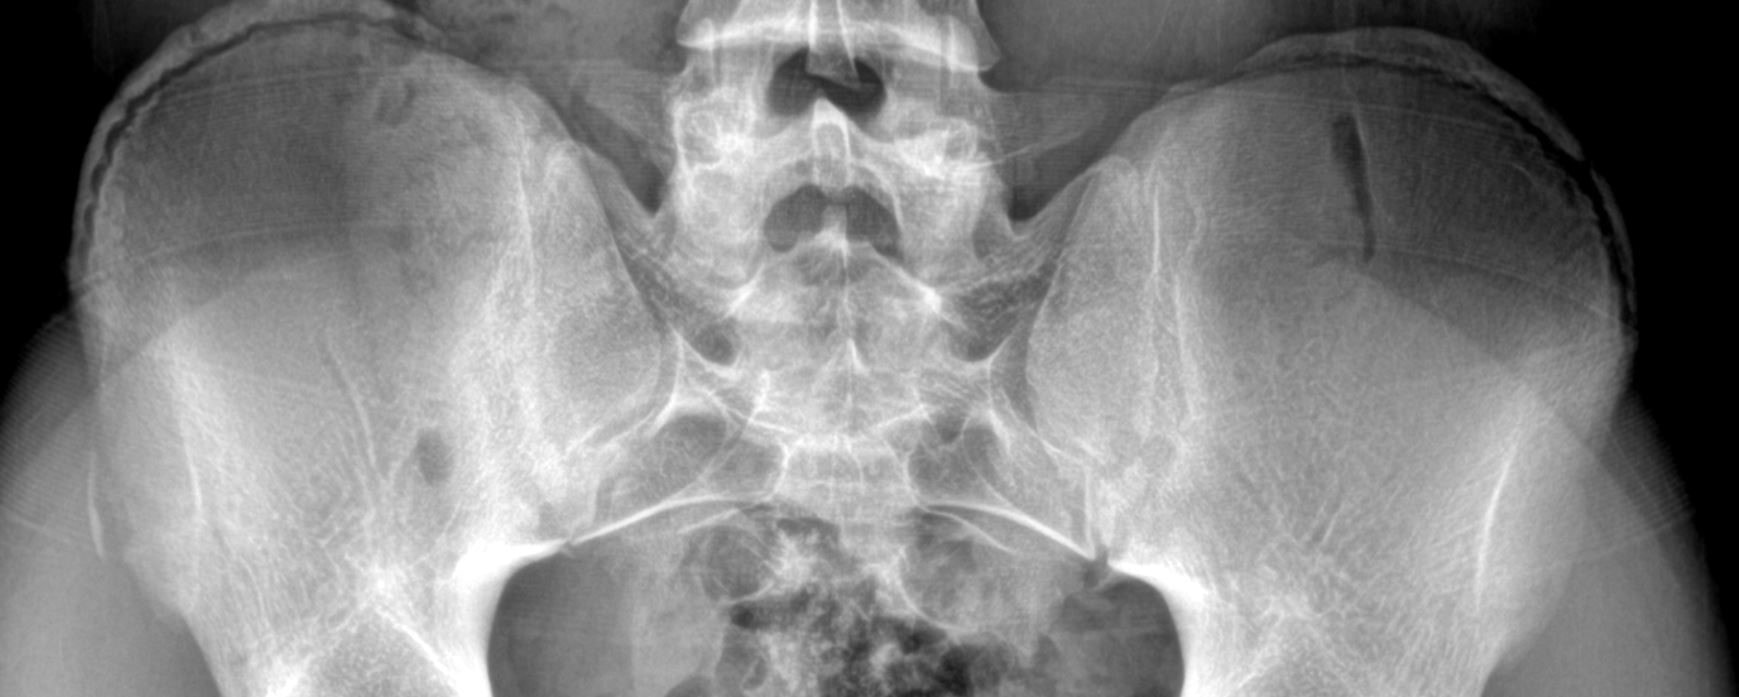

The patient is a 12-year-old boy who presents with sudden hip pain that started simultaneously with a “popping feeling” in the same hip. He reports that it started in the middle of his football game earlier in the day.

View the image taken and consider what the diagnosis and next steps would be. Resolution of the case is described on the next page.

A 12-Year-Old Football Player with Sudden Hip Pain